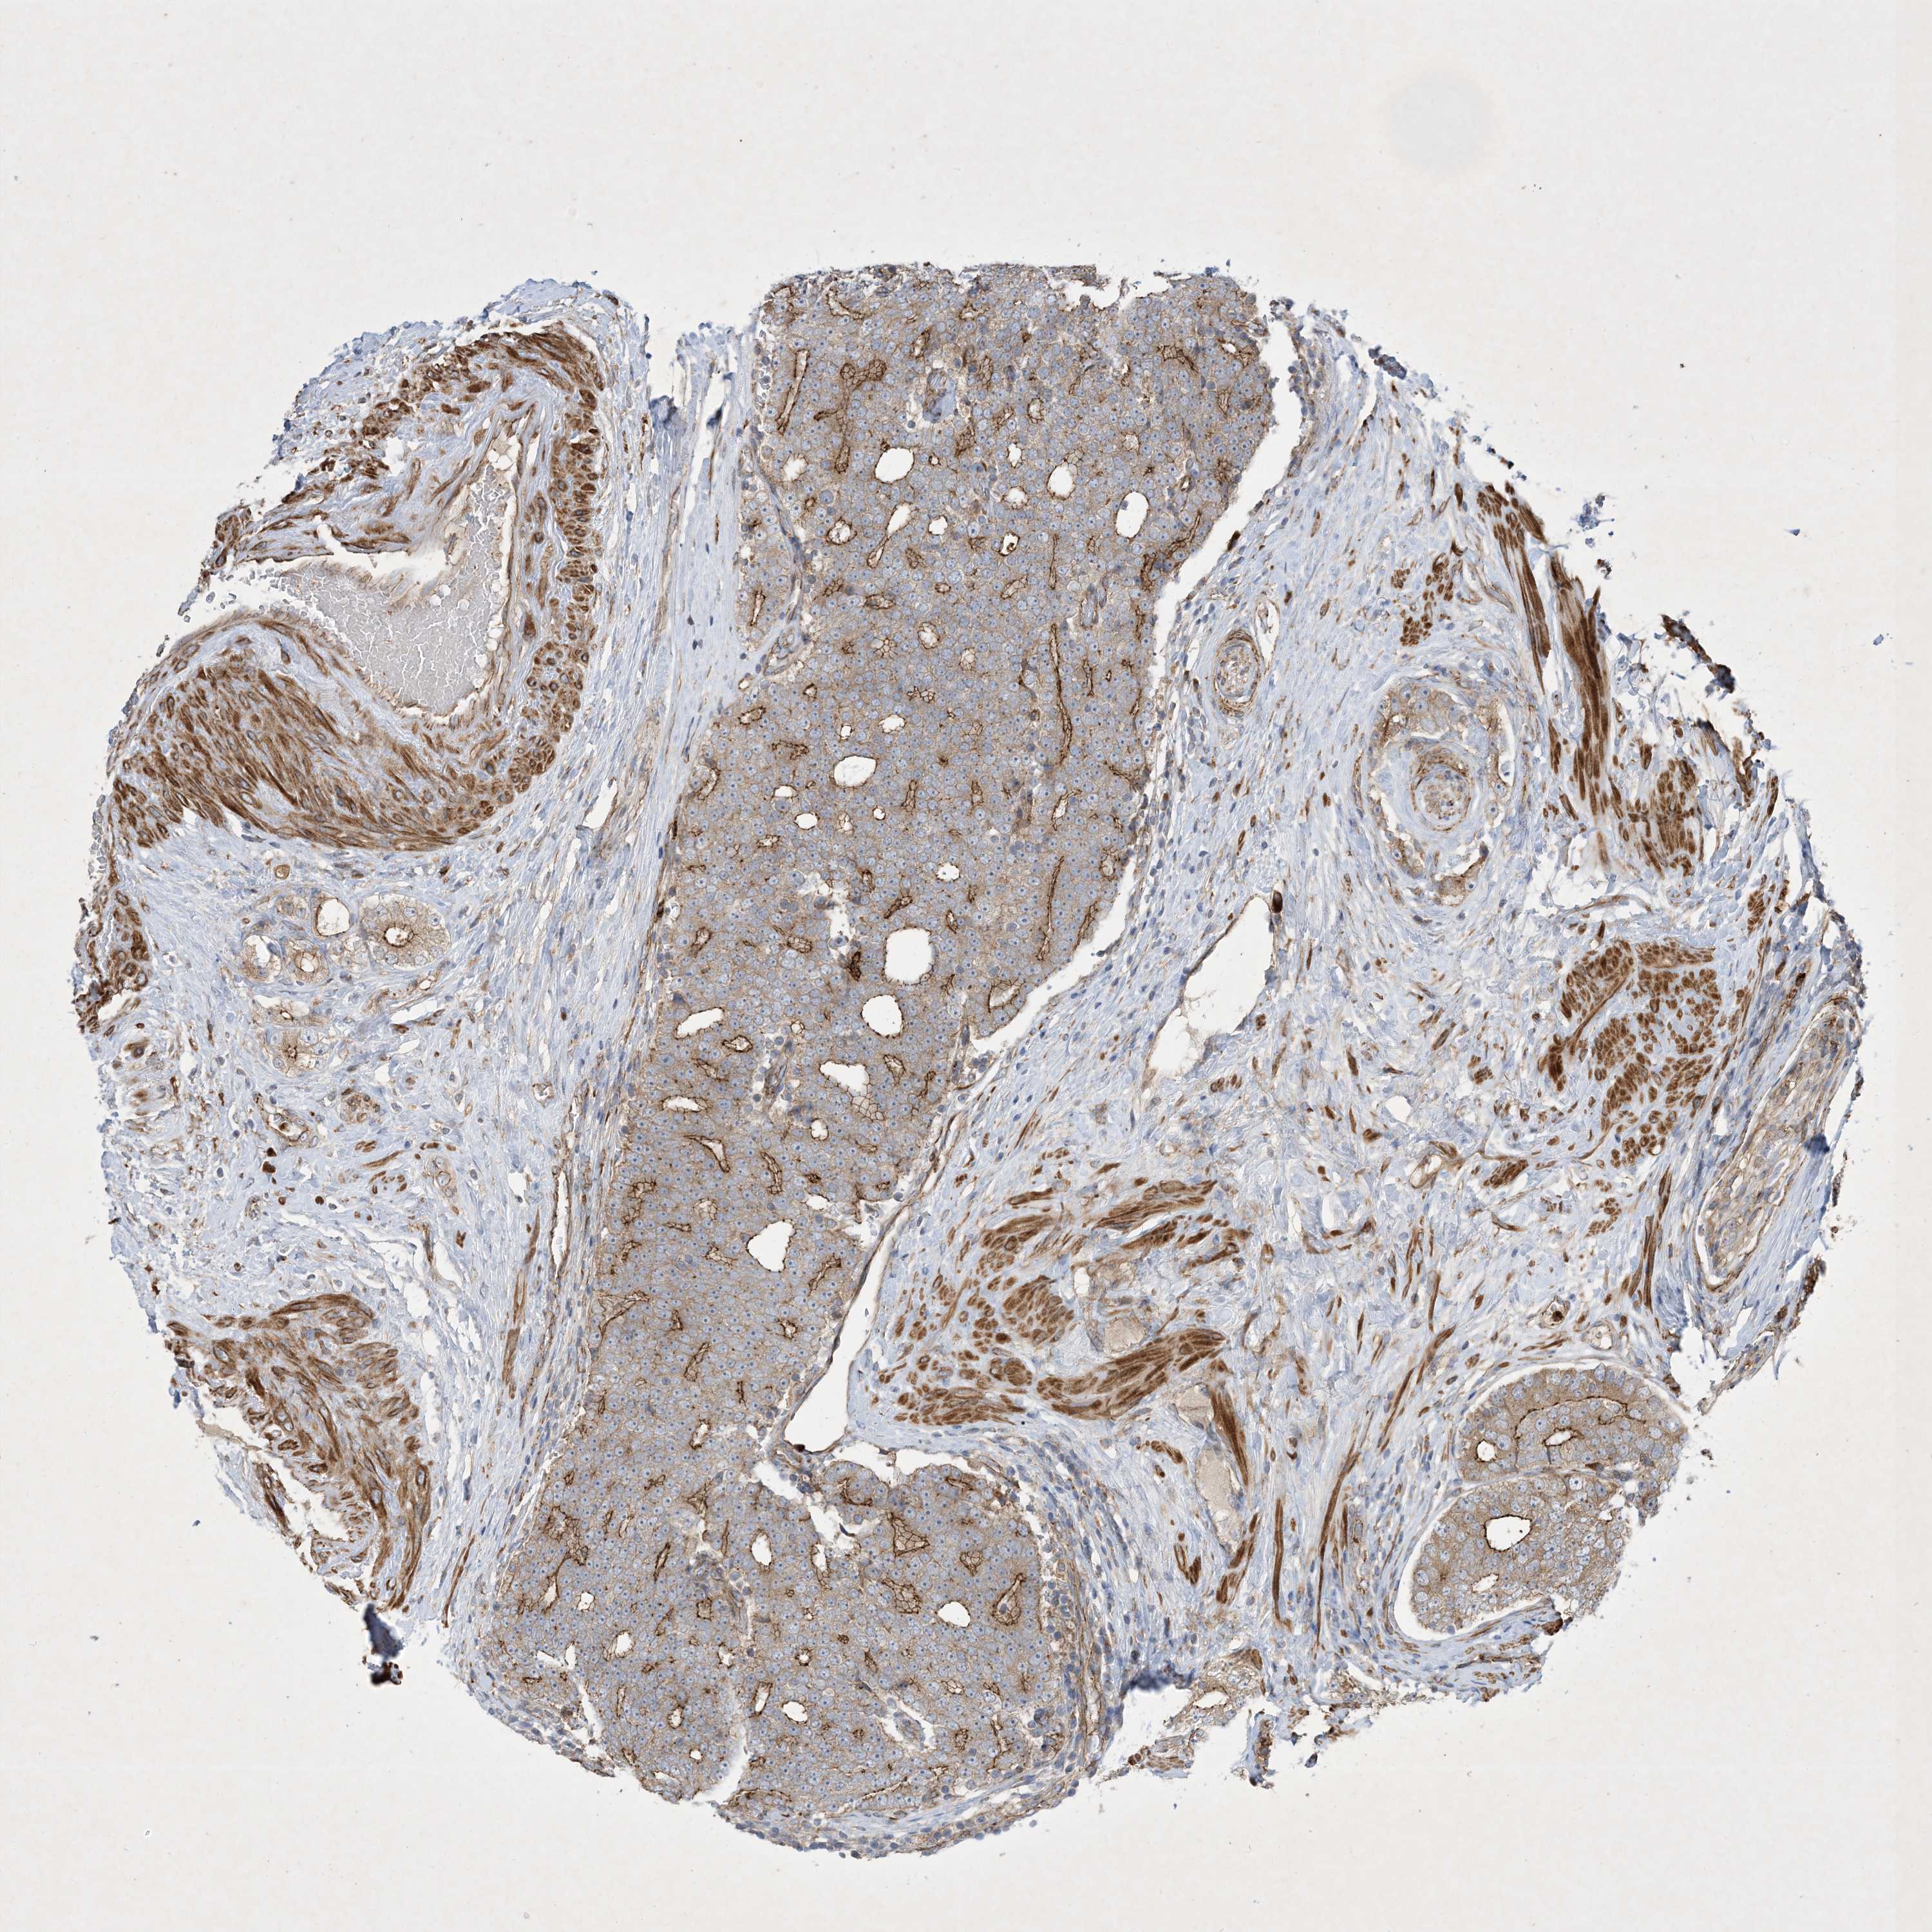

PROSTATE CANCER - Protein expressioni

A mouse-over function shows sample information and annotation data. Click on an image to view it in a full screen mode. Samples can be filtered based on level of antibody staining by selecting one or several of the following categories: high, medium, low and not detected. The assay and annotation is described here.

Note that samples used for immunohistochemistry by the Human Protein Atlas do not correspond to samples in the TCGA dataset.

Antibody stainingi

Antibody staining in the annotated cell types in the current human tissue is reported as not detected, low, medium, or high, based on conventional immunohistochemistry profiling in selected tissues. This score is based on the combination of the staining intensity and fraction of stained cells.

Each image is clickable and will lead to virtual microscopy that enables deeper exploration of all samples and also displays staining intensity scores, fraction scores and subcellular localization as well as patient and tissue information for each sample.

Antibody HPA035599

Staining

High

Medium

Low

Not detected

Intensity

Strong

Moderate

Weak

Negative

Quantity

>75%

75%-25%

<25%

None

Location

Nuclear

Cytoplasmic/membranous

Cytoplasmic/membranous,nuclear

Adenocarcinoma, High grade

Adenocarcinoma, Low grade